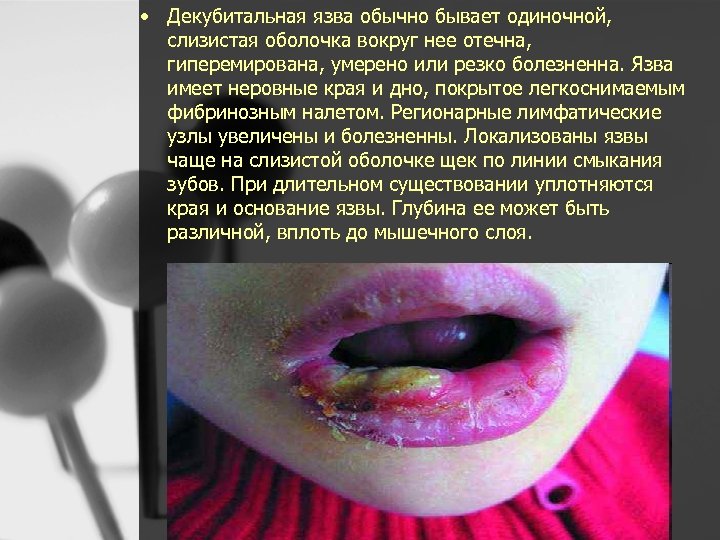

КЛИНИЧЕСКАЯ КАРТИНА • Отмечают незначительную болезненность на месте прикусывания щеки и губ. При внутритканевом кровоизлиянии через 1– 3 дня выявляют гематому синюшно черного цвета. В месте повреждения происходит образование инфильтрированной в основании болезненной эрозии, которая обычно быстро эпителизируется. В случае вторичного инфицирования эрозия может перейти в длительно незаживающую язву

• При прикусывании щеки и губ, поражениях слизистой оболочки полости рта общее состояние ребенка не нарушено, сон спокойный, температура тела нормальная. При дефектах верхних слоев эпителия, возникающих в результате привычного прикусывания слизистой оболочки, прием пищи безболезненный, дети жалоб не предъявляют. Врач обнаруживает такие поражения, осматривая слизистую оболочку полости рта при проведении плановой санации. Слизистая оболочка обычной окраски, в местах травмирования (в области щек, губ), ее поверхность неровная, видны обрывки эпителия белого цвета, иногда небольшие кровоизлияния. Пальпация слизистой оболочки у таких детей обычно безболезненна. • Травматические эрозии имеют неправильную форму, покрыты тонким фибринозным налетом беловато желтоватого цвета, окружающая слизистая оболочка слабо или умеренно гиперемирована. • Декубитальная язва обычно бывает одиночной, слизистая оболочка вокруг нее отечна, гиперемирована, умерено или резко болезненна. Язва имеет неровные края и дно, покрытое легкоснимаемым

• Декубитальная язва обычно бывает одиночной, слизистая оболочка вокруг нее отечна, гиперемирована, умерено или резко болезненна. Язва имеет неровные края и дно, покрытое легкоснимаемым фибринозным налетом. Регионарные лимфатические узлы увеличены и болезненны. Локализованы язвы чаще на слизистой оболочке щек по линии смыкания зубов. При длительном существовании уплотняются края и основание язвы. Глубина ее может быть различной, вплоть до мышечного слоя.